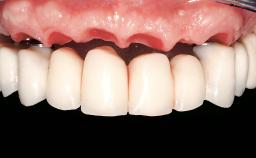

Conventional Loading of Eight Implants in the Maxilla and Final Restoration with a Full-Arch Gold-Ceramic FDP

Prosthesis Type FDP